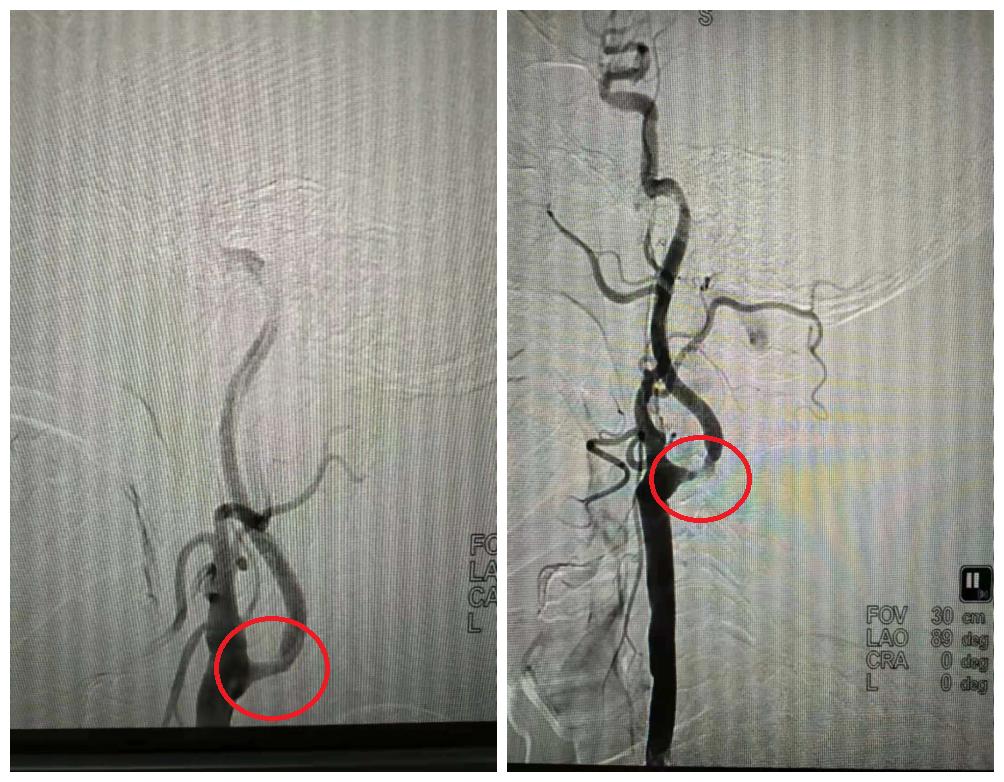

血管球囊扩张成形术和血管内支架植入成型术已经成为治疗脑缺血、脑梗塞十分重要的手段。

手术操作时,在DSA监控下,将导引管经主动脉插到颈动脉或椎动脉(供应颅脑的血管)内,再置放支架,达到扩开狭窄段血管、顺行性血流再建的目的。

右颈C1支架置入术前(左)术后(右)

左颈C1支架置入术前(左)术后(右)